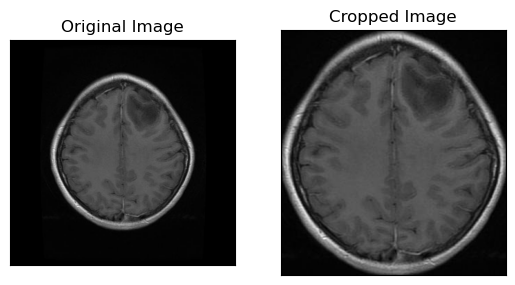

Penggunaan teknik klasifikasi otomatis yang diterapkan pada data hasil pemindaian MRI dapat memberikan kontribusi yang signifikan untuk peningkatan kualitas perawatan pasien dengan tumor otak. Berikut Penerapannya :